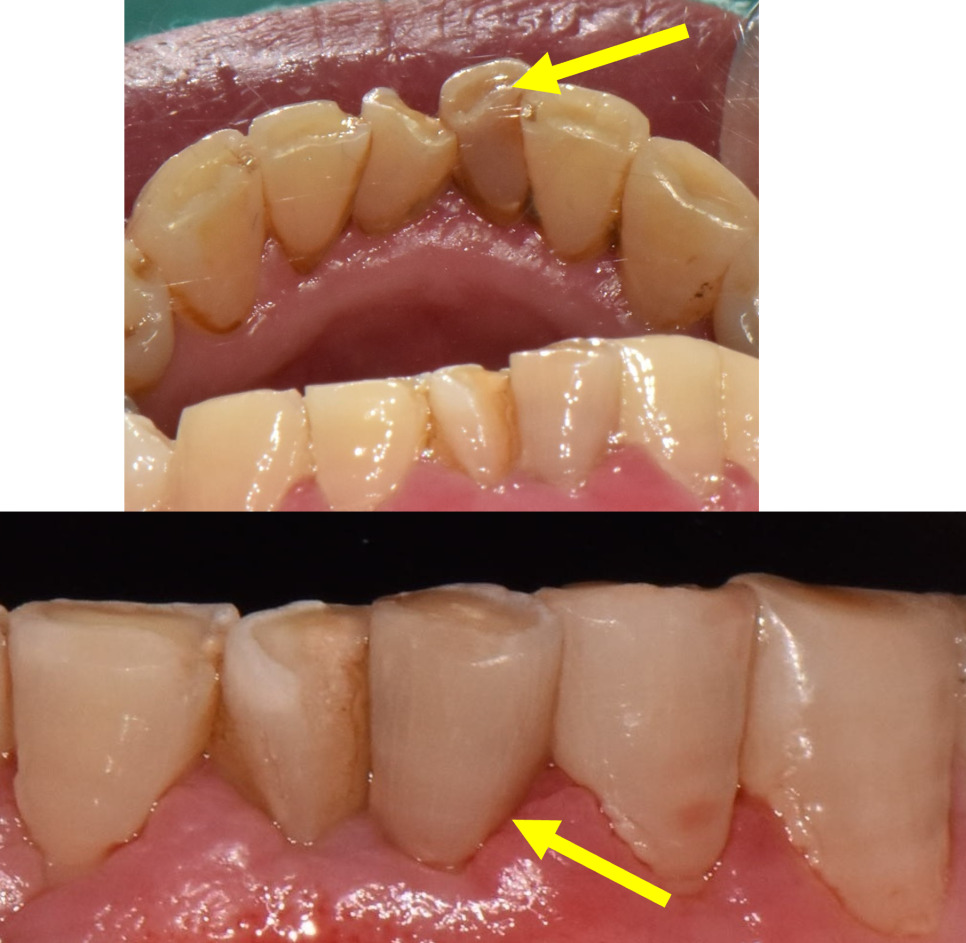

자, 앞니통증이 있는 치아는 뒤에서 살펴보기로하고

고혈압환자의 입안사진부터 쭉 살펴보겠습니다.

노랑색화살표를 보면 앞니가 깨져있습니다.

다른 앞니들의 마모도 상당한 편이네요.

24.02.01(초진) – 69y 김OO님

오른쪽, 왼쪽 측면 사진입니다.

노랑색화살표를 보시면 양쪽 작은어금니들이

전부 깨져있습니다.

아래턱치아들도 볼까요?

노랑색화살표를 쭉 보면

치아가 깨지고, 마모가 심해서

치아를 둘러싸고 있는 가장단단한 부분인

법랑질이 없고,

무르고 신경에 가까운 상아질이

전부 노출되어있습니다.

앞니변색과 앞니통증을 일으키고 있는

치아도 마찬가지입니다.

앞니통증이 심했던 치아를 찾아보니

아래쪽 앞니변색이 심하게 관찰됩니다.

보통은 밖에서 봤을때 변색이 눈에 띄는 편인데,

이 환자분은 혀쪽에서 봤을때

앞니변색이 굉장히 심했습니다.

(위 사진 노랑색화살표)